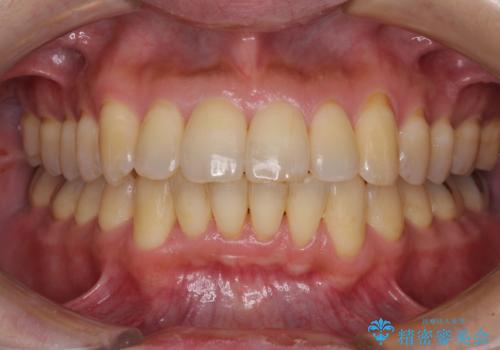

- 口元の閉じにくさと、前歯のでこぼこの歯並びを気にして来院された患者様です。

口元を積極的に引っ込めるために、上下左右の小臼歯計4本を抜歯することとしました。

セオリーでは第一小臼歯を抜歯しますが、上下右側は第二小臼歯に銀歯が装着されているため、第二小臼歯を抜歯することとしました。

上下正中を左右対称に揃えるため、アンカースクリューや補助装置を使用しながら口元を下げていくこととしました。

積極的に前歯を牽引したことで、口元の閉じにくさは顕著に改善され、横顔のシルエットが大幅に変化しました。